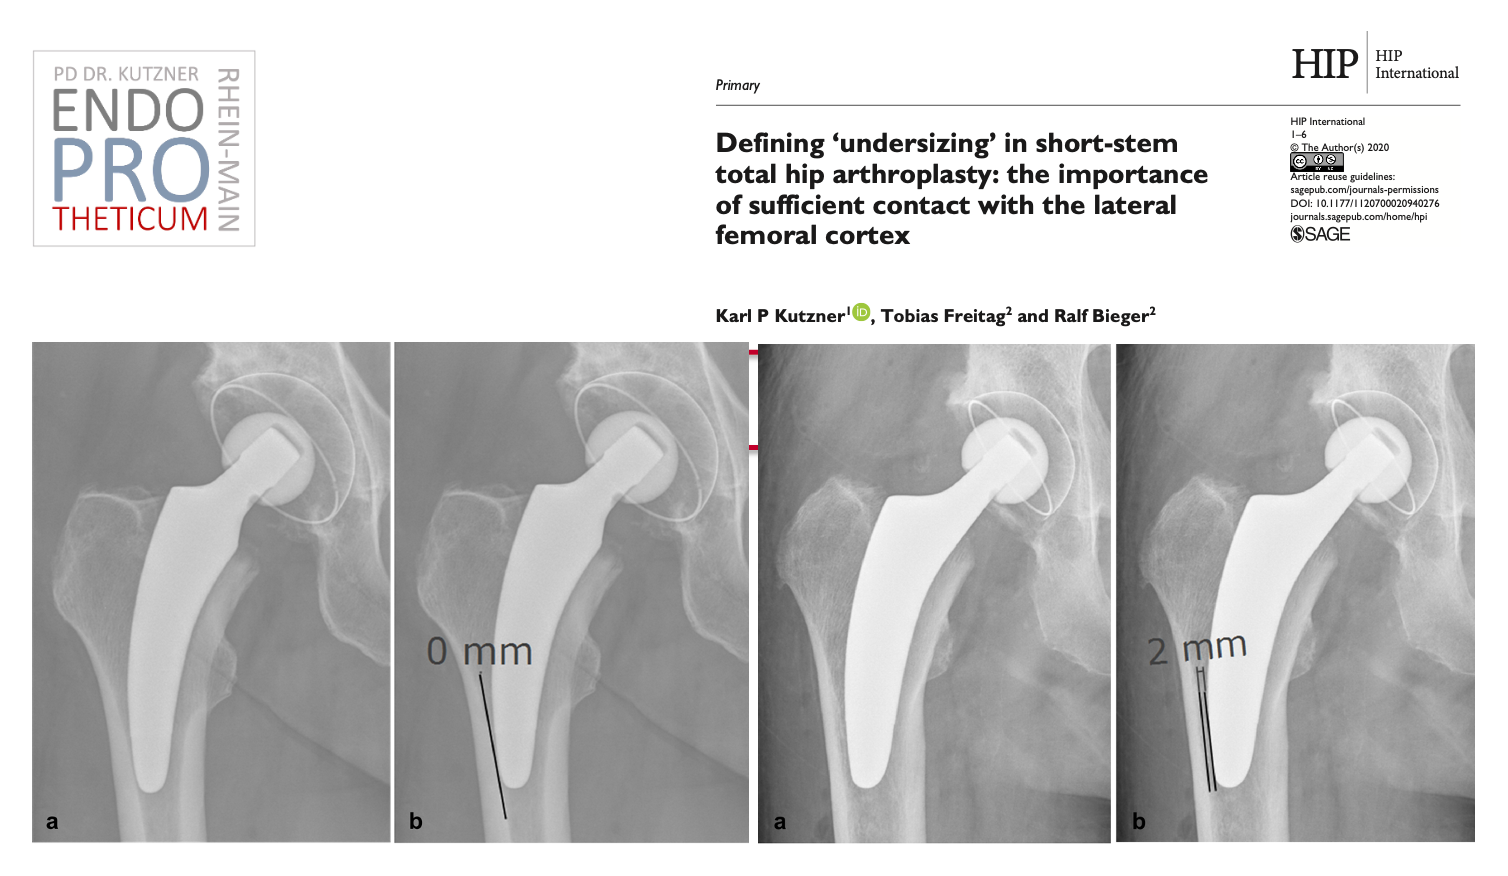

The concept of modern calcar-guided short stems in hip arthroplasty aims at the precise reconstruction of the individual, anatomical hip geometry. This involves a

bone- and soft tissue-sparing implantation technique in conjunction with a physiological load on the joint-proximal part of the femur, used to preserve the bone in the long term.